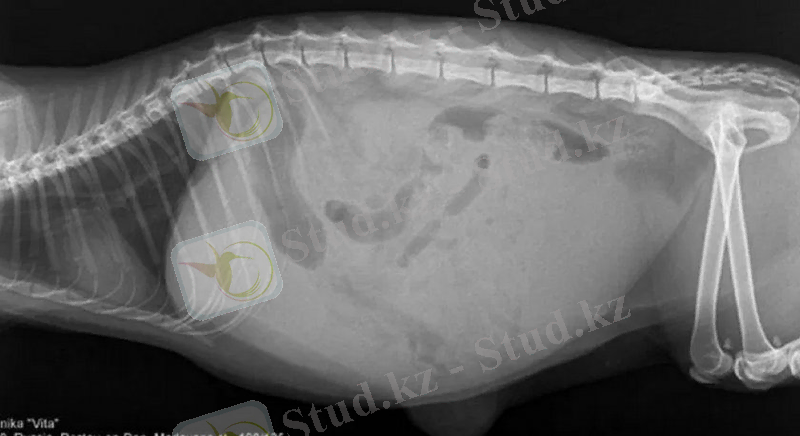

- Іш қуысының рентгенографиясы бұл кезде ішек ішіндегі жиналған нәжісті, немесе ішектің ауруларын анық көре аламыз.

Несеп тас ауруының субклиникалық түрі. Бұл пішінде ит аурудың клиникалық белгілерін көрсетпеуі мүмкін. Иттердегі зәр тастары әртүрлі болуы мүмкін. Иттегі кейбір зәр тастарын рентген сәулелері арқылы анықтауға болады. Кейбір иттерде аурудың бұл түрі зәр шығару жолдарының бір немесе басқа қабынуымен бірге жүреді.